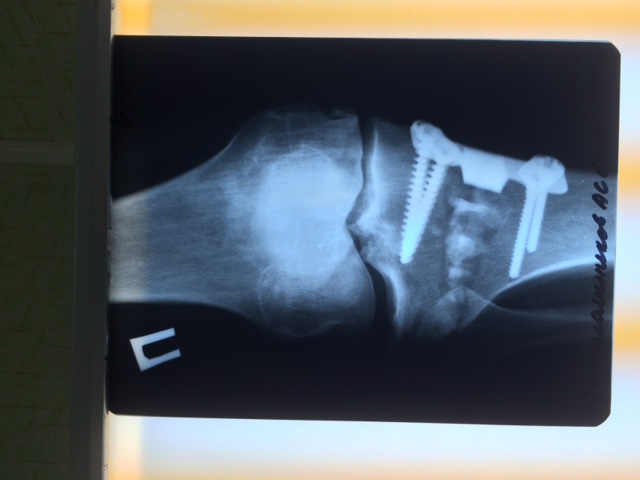

Операция по поводу Hallus Rigidus c использованием современных имплантов системы IO-FIX

Сложная плоско-вальгусная патология стопы Артродез таранно-ладьевидного сустава , 1 плюснеклиновидного сустава, артродез пяточно-кубовидного сустава

Использованы комбинированные методы реконструктивной операции (SCARF+AKIN+ WILSON+ подкожные методы остеотомии малых лучей на левой и правой стопе)

Сложная стопа с выраженным поперечным плоскостопием выполнен ряд оперативных методик реконструкции переднего отдела стопы (SD+AKIN+PROXIMO+WILSON+ WEIL) Использованы импланты SFM, SIF

Сложная прогрессирующая деформация стопы на фоне ревматоидного полиартрита. Выполнены множественные комбинированные методы хирургической коррекции (SD+ AKIN+ артродез LAPIDU + ряд малоинвазивных подкожных остеотомий малых лучей на уровне проксимальных фаланг 2,3,4 пальца ) Использованы специальные импланты винты SFM, титановые скобы и подкожная фреза для аппарата АОК УНИ -01